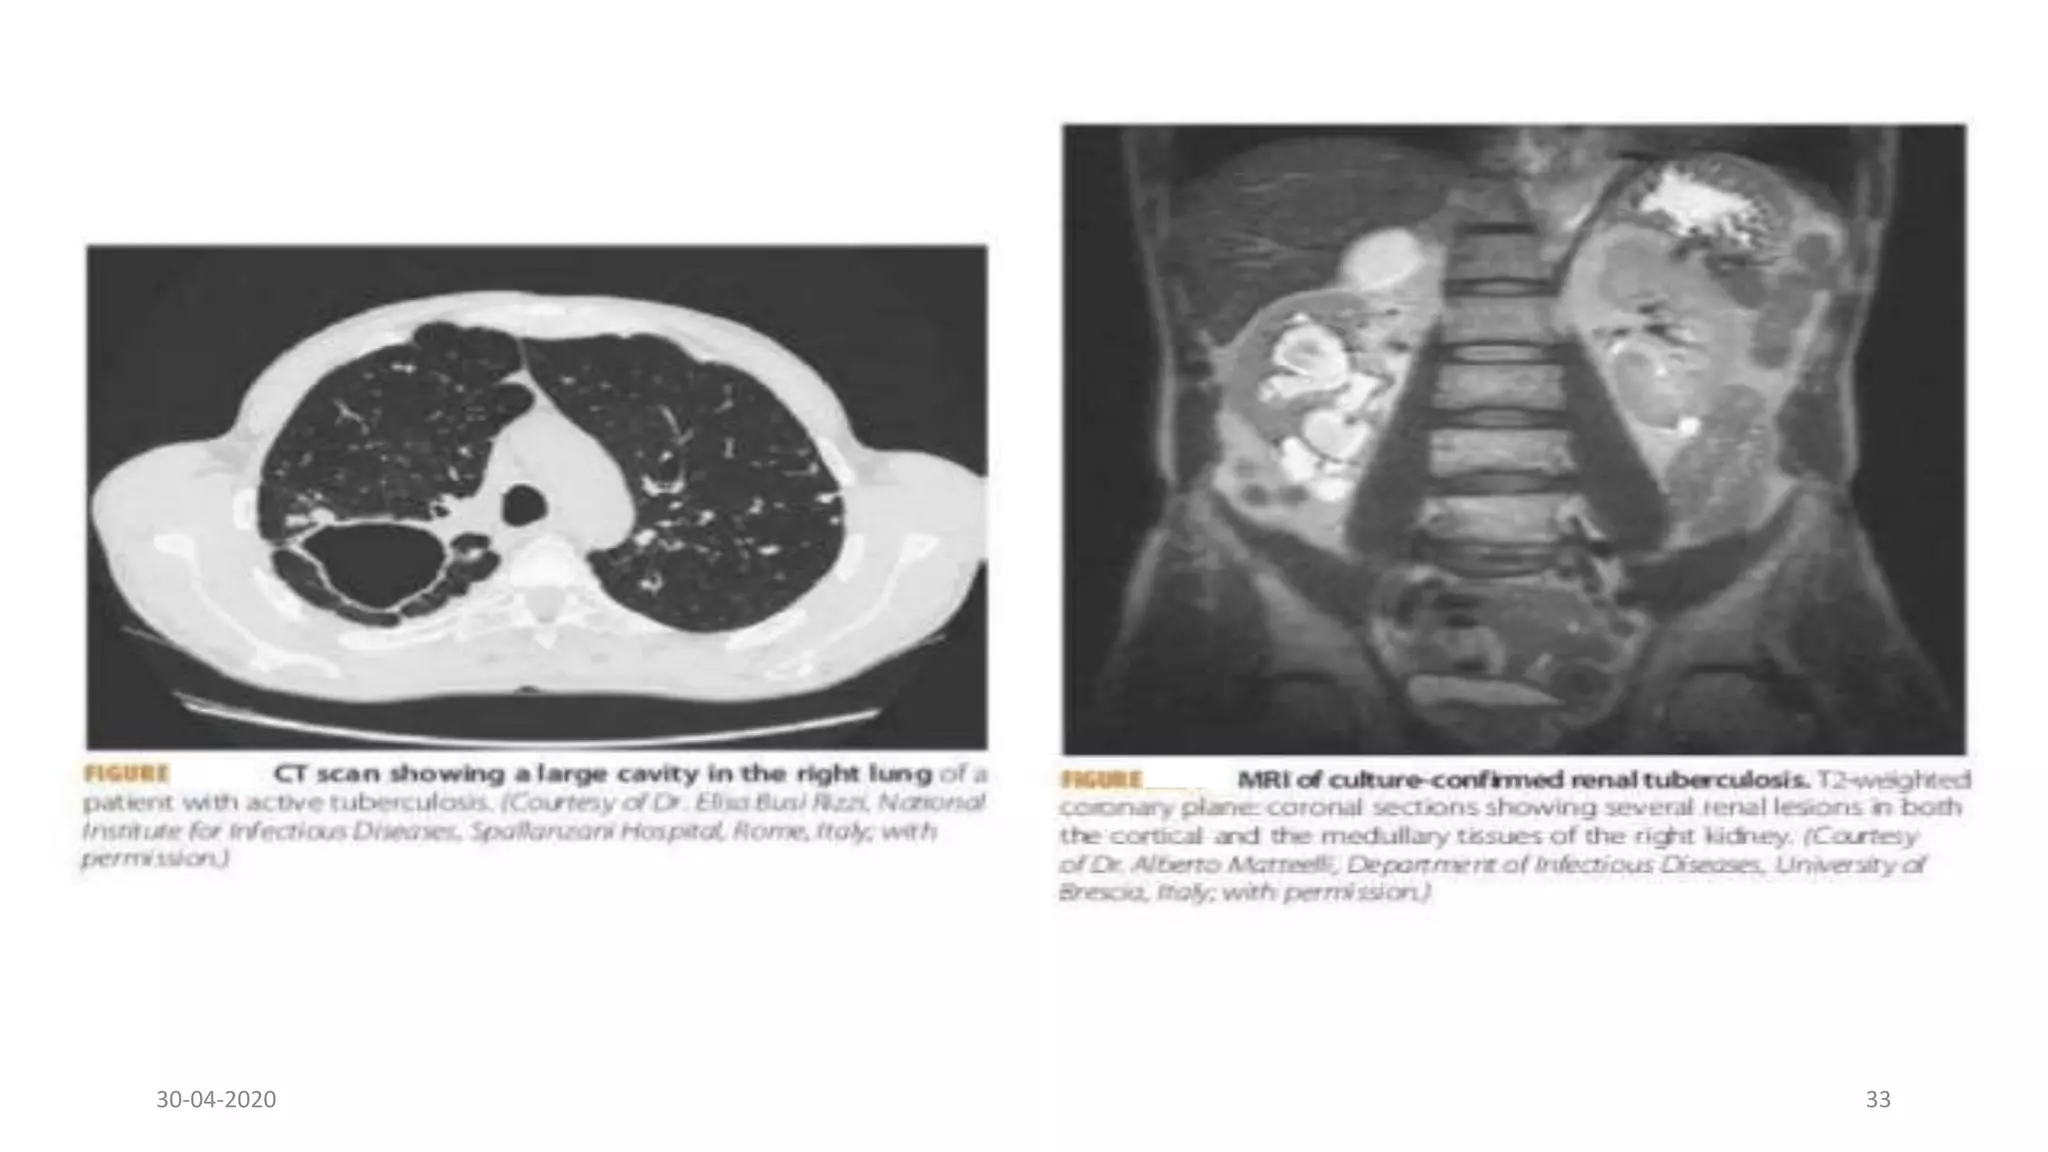

Chest X-Ray

The chest x-ray

may also appear

normal in a

patient with TB.

Findings

suggestive of TB

include upper

lobe infiltrations,

cavitary

infiltrates and

lymph node

involvement.

Chest X-Ray The chestx-ray may also appear normal in a patient with TB. Findings suggestive of TB include upper lobe infiltrations, cavitary infiltrates and lymph node involvement. 30-04-2020 32